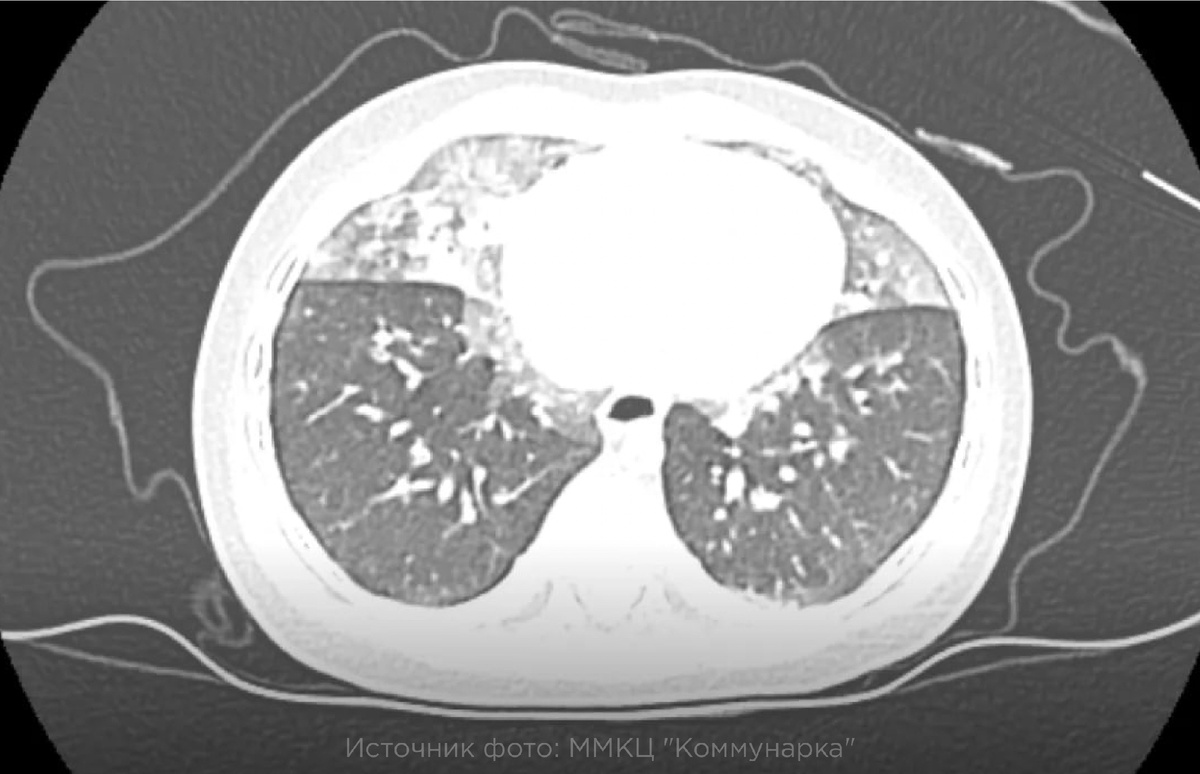

Только на КТ врачи смогли обнаружить участки «матового стекла» — специфический симптом, типичный для нейроэндокринной гиперплазии.